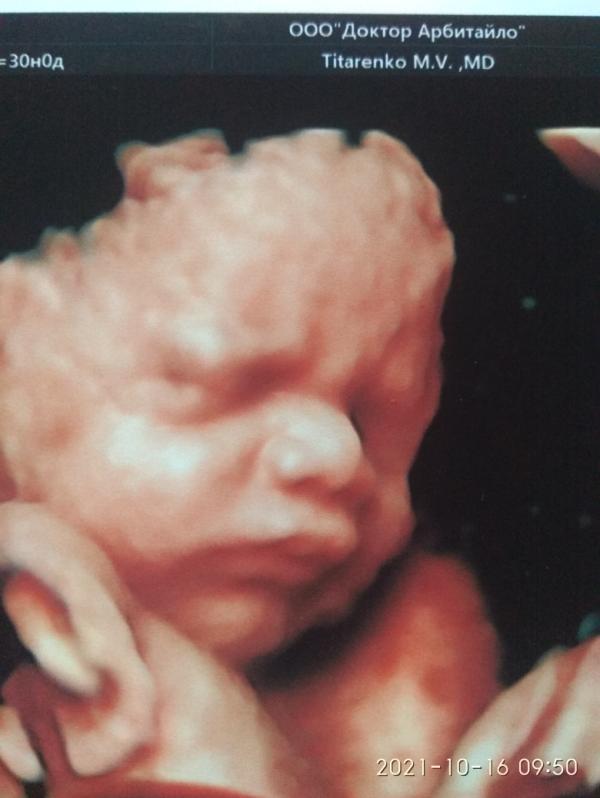

Сходили с мужем и дочкой на 3 скрининг к Титаренко М.В, сказал что вовремя пришли, по первому УЗИ срок 30 недель, сейчас срок показал 31-32 недели, по мес вообще 29.3, малыш растет не по дням, а по часам😁😁😁, вес 1709 гр, сначала фото не давал сделать, потом на бочок легла и фоточки получились суперские, только хмурился долго 😾😾😾.. Но врач еще поставил многоводие легкое, сказал у гинеколога узнать все надо будет, ребенок ложится, то поперёк, то в головное, и обязательно лучше носить бандаж... Вр...